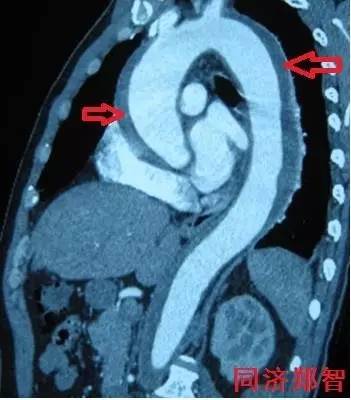

② Stanford A型 主动脉壁间血肿的CTA重建(图2),提示升主动脉和胸降主动脉的主动脉壁均有病变(红箭头所示)。

图2